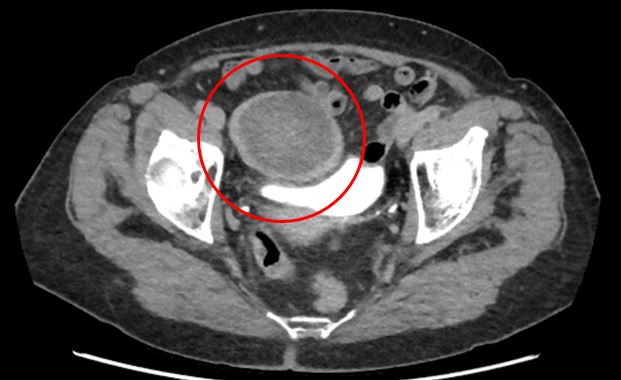

По результатам КТ живота с контрастированием выявлены неорганные образования в брюшной полости, расположенные между петлями кишечника с выраженной фиброзной капсулой, а также состояние после спленэктомии и консолидированные переломы ребер слева. Учитывая анамнез, одним из самых вероятных подозрений стало возможное наличие «инкапсулированных инородных тел».

3. В малом тазу, плотно прилегая к мочевому пузырю, находилось еще одно неорганное образование шаровидной формы размерами около 5 см. Образование в капсуле содержало около 10 мл гноя.